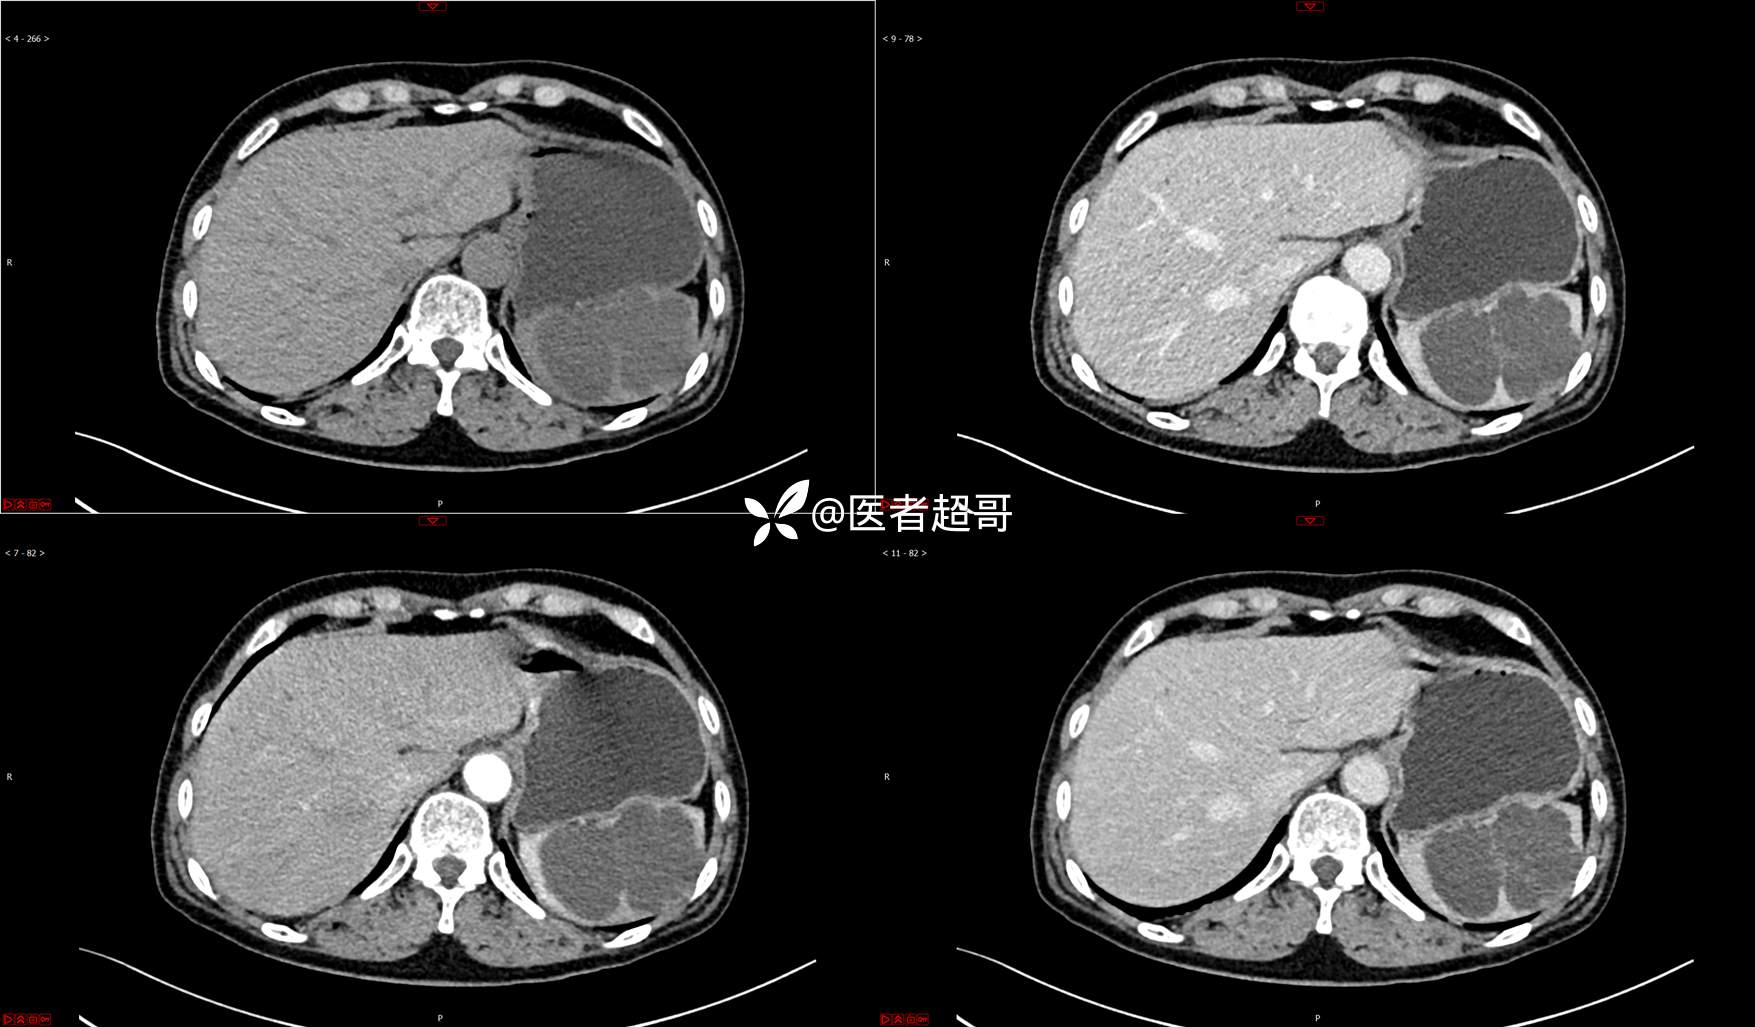

【影诊笔记739】脾脏囊性占位,查体偶发,请赏析,有病理!

主 诉:查体发现脾脏囊性占位4年。

现病史:患者4年前于人民医院查体时发现脾脏囊性占位。-04-20到我院复查,行上腹平扫+强化CT示:肝囊肿,脾脏囊实性占位,囊腺瘤?当时无明显症状,未行任何治疗。4个月前无明显原因及诱因开始偶尔出现左上腹疼痛,为隐痛,伴腰部放射痛,无腹胀、腹泻,无恶心、呕吐,无发热、畏寒、全身乏力,无胸痛、胸闷等其它不适。在外未行特殊治疗,今为求进一步诊治来我院就诊,行腹部彩超(肝、胆、胰、脾、肾)示:脾脏房囊性肿物。门诊以“脾占位性病变”收入院。发病以来,患者神志清楚,精神可,饮食可,睡眠欠佳,大小便正常,近期体重无明显变化。